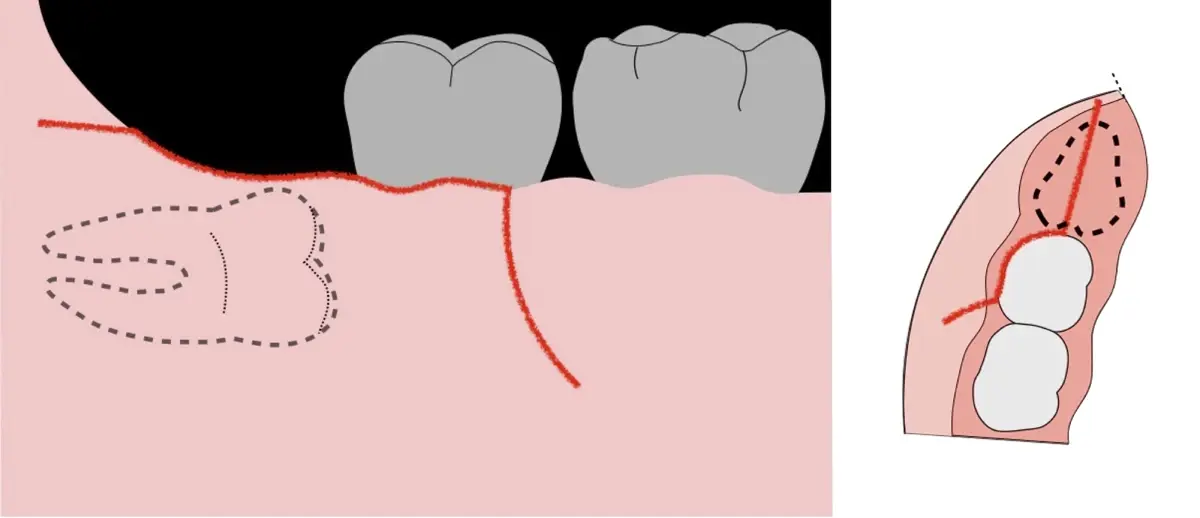

Es imprescindible conocer la ubicación de la tercera molar. Se puede emplear, adicionalmente a la evaluación clínica, herramientas radiográficas (panorámica y periapical) y tomográficas (Cone beam) para determinar la posición, grado de retención y proximidad a estructuras vecinas de riesgo como el nervio dentario inferior y así evitar lesiones (Figura 1).

El procedimiento se inicia colocando anestesia troncular para bloqueo del nervio dentario inferior y sus ramas. Luego, se establecerá el diseño de acceso según la disposición de la molar a extraer. Para fines didácticos, se explicará cómo se realizaría la extracción de la molar de la Figura 1: se realiza una incisión horizontal a nivel de la zona retromolar hasta llegar a distal de la segunda molar, continuándose con una incisión intrasurcular hasta mesial de la segunda molar, finalizando con una incisión vertical a espesor total hasta llegar a la línea mucogingival (Figura 2).